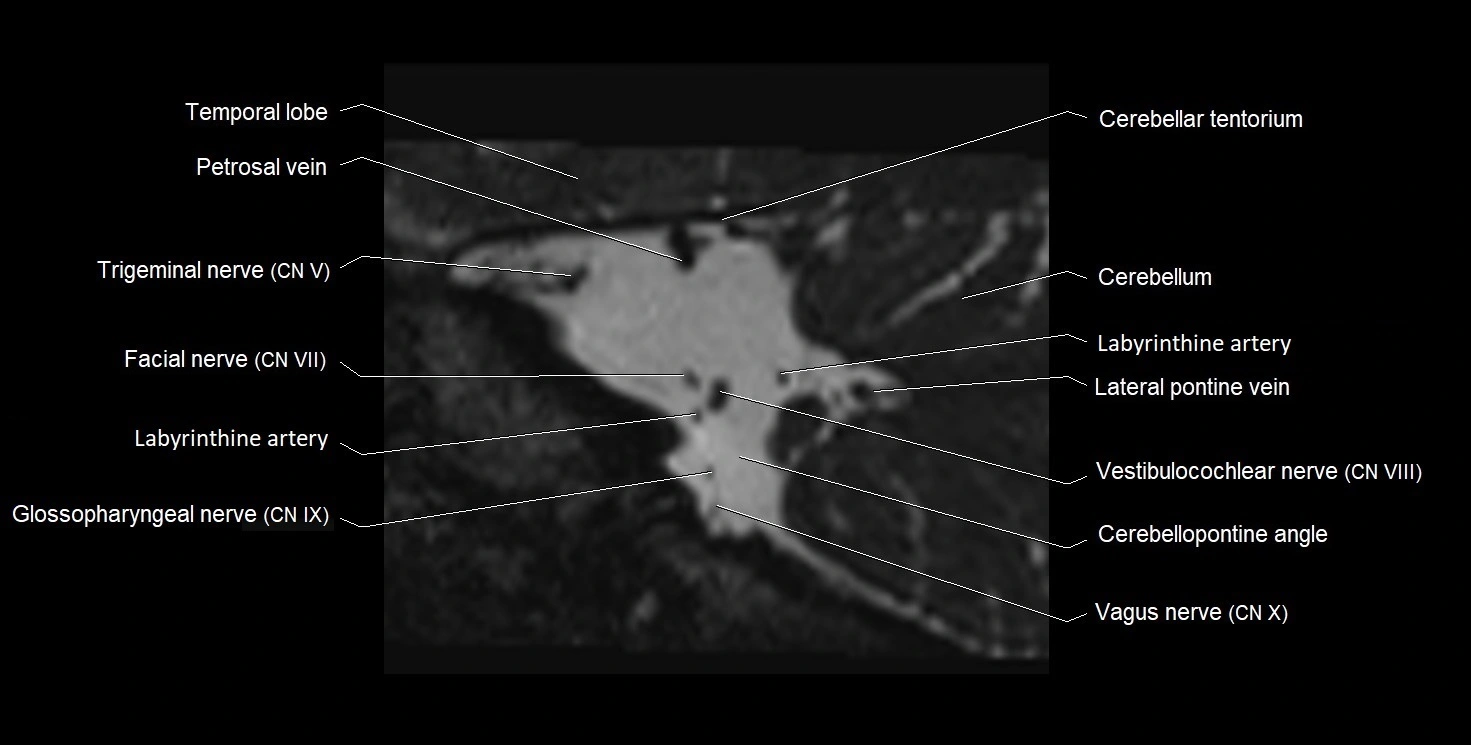

MRI images

image